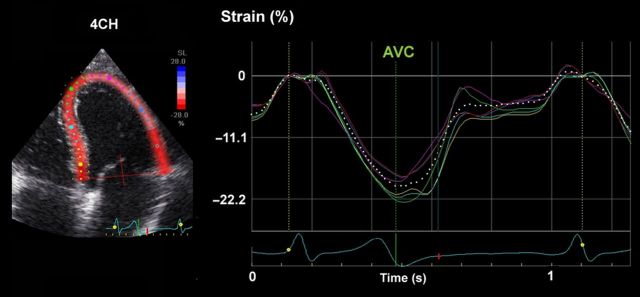

Most laboratories record LV strain in the long axis and use global longitudinal strain (GLS) calculated as the average from all segments, as a measure of global LV function. Figure 1 shows typical segmental strain traces in a normal heart. Images for GLS are made in standard apical two-, three-, and four-chamber views and aortic valve closure (AVC) is used for timing of end-systole.10 When regional speckle tracking is suboptimal and recordings need to be rejected in more than two myocardial segments in a single view, the calculation of GLS should be avoided10 and other methods for measuring global LV function should be used. Normal GLS for most echocardiography systems is reported between 18 and 25% in healthy individuals, a variation, which in part may be explained by inter-software and inter-vendor variability. Technically, good recordings can be achieved along any axis, but interpretation of radial and circumferential strains are complicated by substantial transmural non-uniformity in the normal left ventricle. Figure 2 illustrates and explains this phenomenon which is entirely a geometric effect and does not imply differences in contractility between LV wall layers. For longitudinal strain, however, such geometrical effects are of less magnitude.

Figure 1.

Segmental strains in apical four-chamber view, showing normal contractions. The color of each trace corresponds to anatomical points on the 2-D color image to the left. The white dotted line represents average strain.